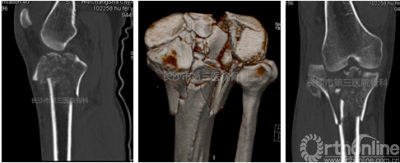

术前计算机辅助钢板设计

术前3D打印模型

首先利用3D打印技术将患者患处骨折打印出模型,通过分析骨折的具体情况后决定将内侧柱和后柱的固定通过一块数字化订制钢板来完成。确定思路后,在雷青主任的指导下进行了该订制钢板的初步设计,然后与钢板制造厂家进行商讨并最终确定了钢板的设计方案。